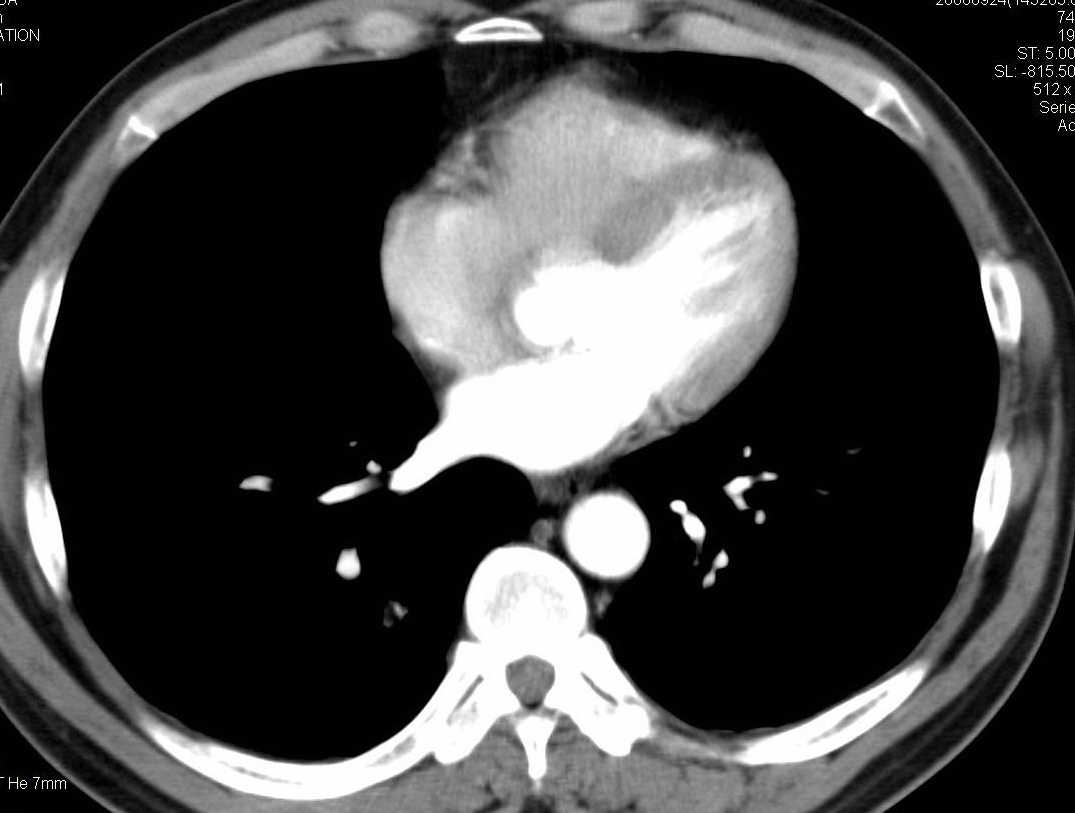

标题: CT15857:男性 58岁 咳痰带血 无发热 请各位大侠发表一下意见 [打印本页]

标题: CT15857:男性 58岁 咳痰带血 无发热 请各位大侠发表一下意见

两肺下叶肺纹理增多、增粗并呈“树芽状”改变。支气管扩张呈囊状,部分呈柱状改变。其周围可见散在的斑片样及条索样密度增高影,右肺下叶近叶间胸膜可见一形态不规则的高密度结节影,并与胸膜粘连。

考虑:支扩并发感染。

双肺多发炎性病灶,结核可能性大,建议抗炎治疗复查.右肺下叶前基底段结节灶,高度警惕肺癌可能

双肺间质性改变(间质纤维化?)伴支扩。右肺下叶有毛刺的小结节,考虑周围型肺癌可能性。